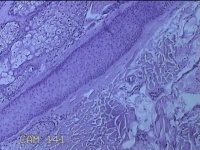

头皮结节

性别

男

年龄

33岁

临床诊断

皮肤赘生物

一般病史

发现头皮结节半个月余,无明显疼痛及不适。

标本名称

大体所见

灰白暗红色带皮肤样结节1x0.8x0.3cm一个,表面糜烂,切开结节呈实性,切面灰白粉红色,质软。

图4